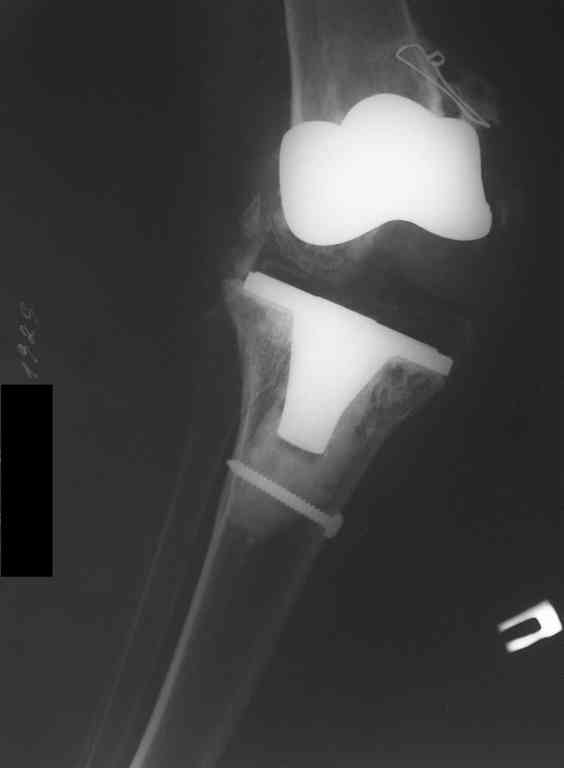

This patient is a 78 y o woman, she has osteoarthritis.3 years ago she had a total right knee replacement (Zimmer LPC).

after she started towalk without a cane,she felt that her knee is (giving way).the clinical knee examination showed medial knee instability and valgus deformation of this knee.2 years ago MCL repair was achieved……and no improvement.A year ago,she had knee replacement for this knee for the second time with bigger-sized implant and no improvement…now she using crutches and knee orthosis. In attachments ,2 monthes ago x-ray images.Any suggestion?